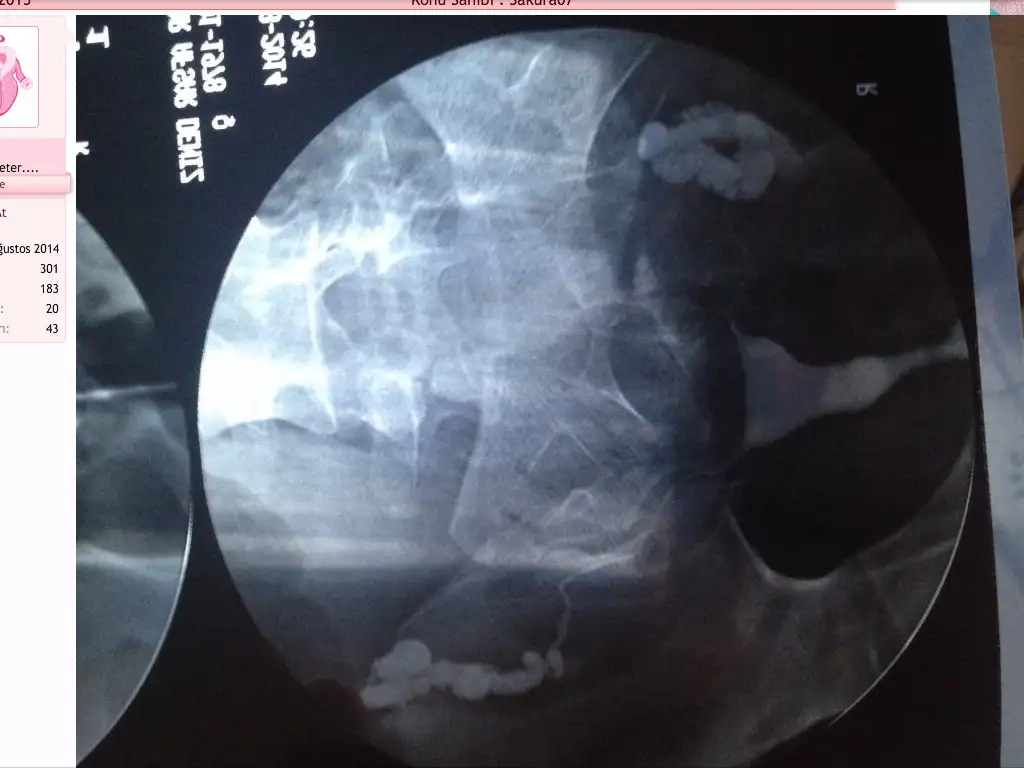

HSG filmimde tüplerin tıkalı ve sıvı birikimi dışında rahim şekli ile ilgili bir sıkıntı varmı acaba

merhabalar : her ıkı tupunuzün hıdrosalpinx (içi sıvı dolu şiş tupler)gorunumu mevcut.

hidrosalpinx : yumurtayla spermin karsılastıgı yer olan tubal bölgede sıvı toplanmasına hidrosalpinks denir.

1. Hidrosalpinks sıvısının İçerdiği mikroorganizmalar ve endotoxinler nedeniyle direk embriyo üzerine zararlı etki (embriyotoksik etki)

2. endometriyumun embriyoyu kabul etme yeteneği’nin bozulmasına ve tutunma potansiyelinin azalmasına neden olmaktadır.

Tüm bu veriler doğrultusunda hidrosalpinksli hastalarda implantasyon ve gebelik oranlarını iyileştirmek için salpenjektomi (tüpün çıkartılması) ile hidrosalpinksli tubanın ortamdan uzaklaştırılması dogru bır yaklasım olucaktır.Sızın her ıkı tupunuzun laparoskopı ( kapalı amelıyat) ıle degerlendırılmesı ve bu duruma yol acan yapısıklık durumları var ıse acılması ancak acılamıyor ıse ve tüpten gecıs saglanamıyor ıse saglıksız tuplerın alınması faydalı olucaktır.